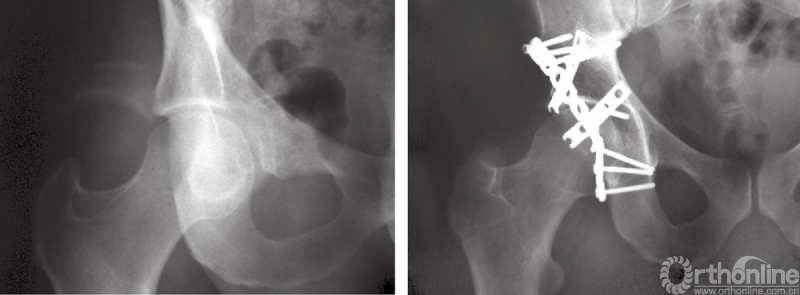

A和B髋臼后壁合并后柱骨折的固定

45岁男性患者,交通事故导致左侧髋臼后柱及后壁骨折。注意骨折线向上延伸以及髋臼顶的骨块。选择后侧入路,以两块钢板固定。同时进行关节囊外大转子截骨并以两枚螺钉固定。